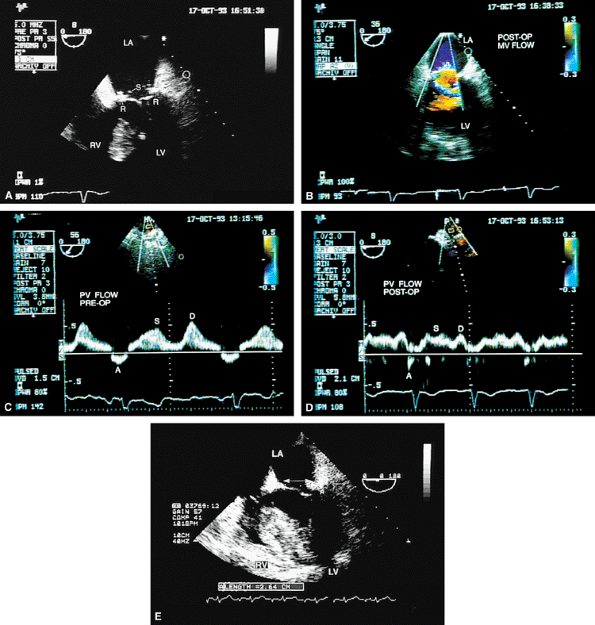

FIGURE 5.13. Mitral annuloplasty ring. A. R demonstrates an annuloplasty ring in the mitral position. S, sutures. B. Color Doppler examination shows aliased inflow signals and prominent diastolic flow acceleration (arrow) produced by narrowing of the mitral orifice by the ring. C. Pulsed-Doppler examination of the left upper pulmonary vein (PV) shows a smaller S wave than D wave, consistent with moderate mitral regurgitation (MR) preoperatively. After ring placement, the S wave is equal to the D wave, suggesting a reduction in mitral regurgitation (in D). E. Another patient in whom the annulus size was reduced to 2.64 cm after placement of an annuloplasty ring for severe MR. LA, left atrium; LV, left ventricle, RV, right ventricle. |